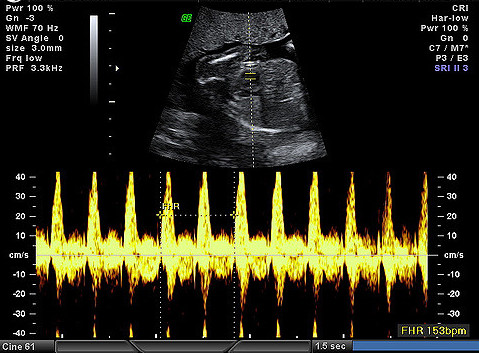

A sonogram and Doppler visualization, Image by Flickr User DYT, (CC BY-NC-ND 2.0)